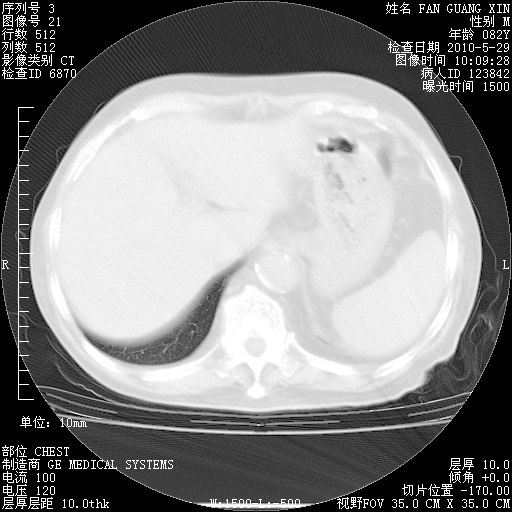

治疗3周后的肺部CT纵隔窗

再治疗10天后的肺部CT

再治疗10天后的肺部CT 纵膈窗